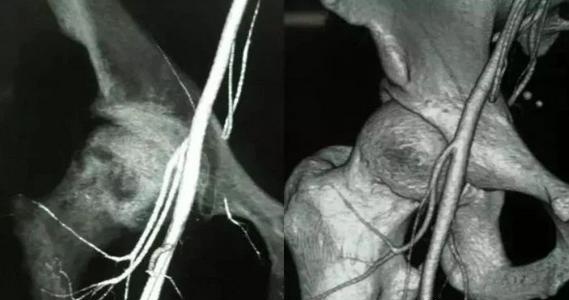

股骨头只有三根主要的血管动脉供应,如果三大供血动脉栓塞,就会导致供血不足,骨细胞就会慢慢“饿”死(此时,患者就会感到剧烈疼痛),从而引起骨细胞或股骨头缺血性坏死,因此股骨头坏死的治疗关键在于堵塞的这三大动脉血管。

⒈ 旋股外侧动脉:

发自股深动脉根部的外侧壁,在缝匠肌与股直肌深面行向外侧,分为升、降两支。

⒉ 选股内侧动脉:

旋股内侧动脉起于股深动脉根部的内侧壁,行向后内,在耻骨肌与髂腰肌之间进入深部,绕行股骨颈内侧至颈内侧到达臀部,是股骨头最主要的供血源。

⒊ 股骨头韧带动脉:

从髋内动脉发出的闭孔动脉的分支股骨头圆韧带动脉,提供股骨头凹部的血液循环,股骨干动脉升肢的发源地。